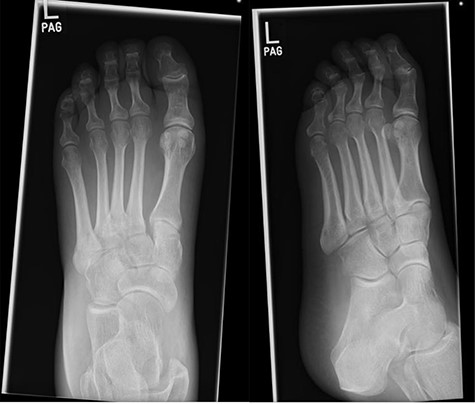

MR images, correlating plain film findings of acute mid-foot destructive changes; typical ‘rocker bottom’ appearance of plantar aspect of foot is seen.

At this presentation, plain film X-ray revealed complete fracture dislocations of the second to fifth tarsometatarsal joints, involving the lateral, middle and medial cuneiform bones of the left mid-foot (Lisfranc fracture dislocations; Fig. 3). This was correlated with bone CT (computed tomography) and MR (magnetic resonance) imaging, with interval changes noted to be of rapid onset (Fig. 4).